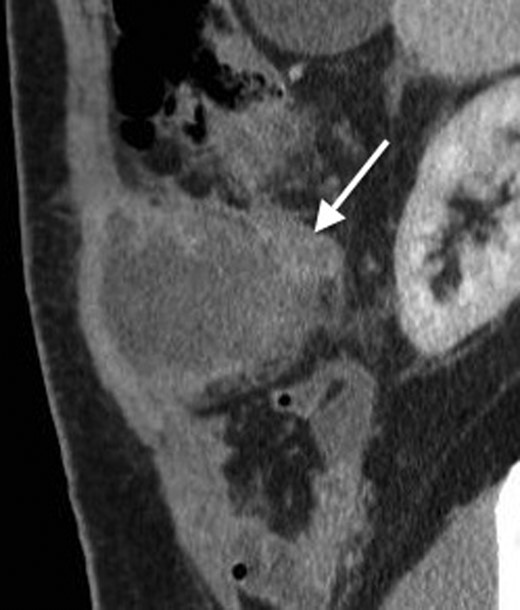

His past surgical history included conservatively managed renal calculi and left inguinoscrotal herniorrhaphy. Right hypochondrial palpation identifying a tender, well-defined, hard, smooth edged, non-pulsatile, non-fluctuant mass (10 × 9 cm). Observations were within normal limits and systemic examinations unremarkable. Haematological results showed the following: albumin 27, WCC 15.7, neutrophils 11.0, CRP 341, amylase 20. Urinalysis, chest and abdominal radiographs (AXR) were normal. Initial resuscitative management was commenced and a contrast enhanced computed tomography (CT) performed. This demonstrated an anterior abdominal wall collection (7 cm) arising from an RUQ appendiceal abscess secondary to acute appendicitis (Figs 1 and 2). Consequent ultrasound (US) guided drainage and pigtail catheter insertion removed 50 ml of frank pus, which isolated pathogens sensitive to penicillin and erythromycin. Following 3 days of intravenous piperacillin and tazobactam (Tazocin®) he was discharged with oral erythromycin. An out-patient barium follow-through and colonoscopy were unremarkable.

An axial CT with contrast showing the RUQ appendiceal abscess.